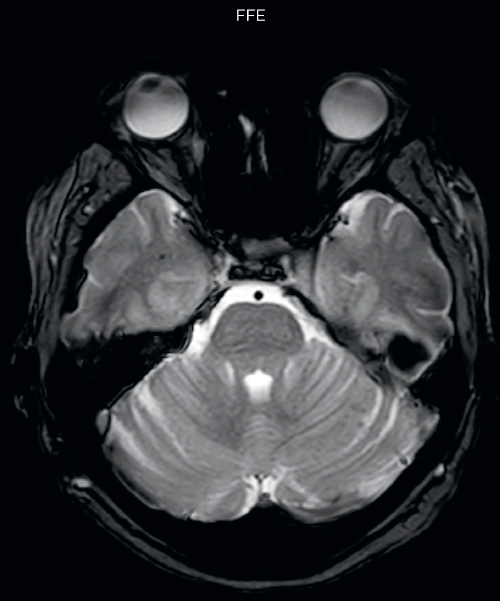

Hemosiderin foci in brain

Gradient echo imaging and SWIp are compared in a patient with radiation-induced foci of hemosiderin deposition. A greater number of small foci is seen on the SWIp image. Ingenia 3.0T

UVM case 1 FFE hemosiderin foci in brain1

UVM case 1 SWIp hemosiderin foci in brain1

“With SWIp we are basically looking for blood byproducts. It is a sensitive method for visualizing small lesions containing deoxygenated blood. In our comparison, SWIp images are vastly better than gradient echo imaging, there’s no question of that anymore.”

“We find the SWIp images very useful in three areas in particular. In patients with a history of hypertension, it offers clear visualization of hemosiderin deposition from hypertensive hemorrhages. We certainly see a greater number of foci of hemosiderin deposition on the SWIp images than on the T2* gradient echo images. In addition, it also helps us visualize amyloid depositions in patients with amyloid angiopathy.”